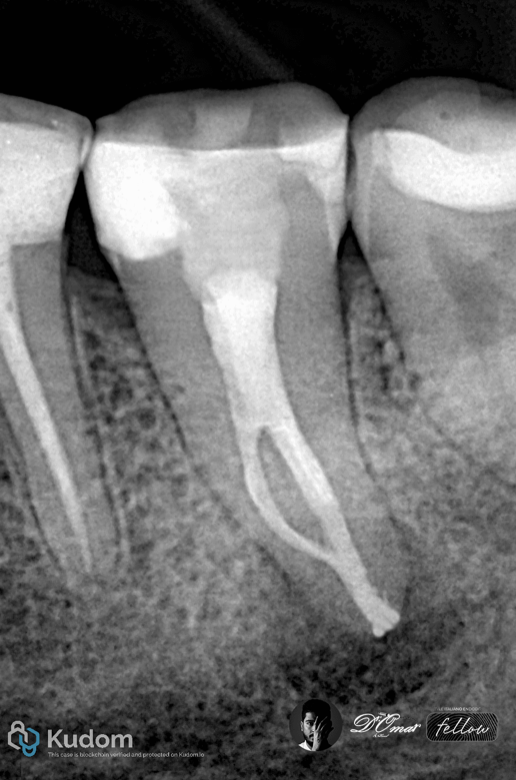

Fig. 2

Working length established using apex locator and radiographs

Rotary NiTi instrumentation to full working length

Irrigation using NaOCI with ultrasonic activation

EDTA for smear layer removal

Fig. 3

Obturation done by BC sealer

with warm vertical compaction

Two-canal mandibular molars typically consist of one mesial and one distal canal, often with round or oval cross-sections. These canals are usually wide, relatively straight, and accessible, allowing efficient mechanical shaping and irrigant penetration.

Such anatomy provides:

-Better irrigant flow

-Fewer uninstrumented recesses

-Higher obturation predictability